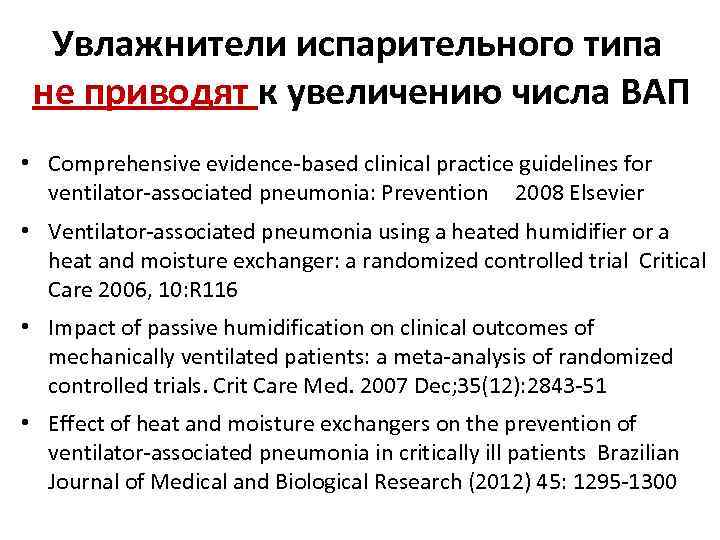

Увлажнители испарительного типа не приводят к увеличению числа ВАП • Comprehensive evidence-based clinical practice guidelines for ventilator-associated pneumonia: Prevention 2008 Elsevier • Ventilator-associated pneumonia using a heated humidifier or a heat and moisture exchanger: a randomized controlled trial Critical Care 2006, 10: R 116 • Impact of passive humidification on clinical outcomes of mechanically ventilated patients: a meta-analysis of randomized controlled trials. Crit Care Med. 2007 Dec; 35(12): 2843 -51 • Effect of heat and moisture exchangers on the prevention of ventilator-associated pneumonia in critically ill patients Brazilian Journal of Medical and Biological Research (2012) 45: 1295 -1300

Увлажнители испарительного типа не приводят к увеличению числа ВАП • Comprehensive evidence-based clinical practice guidelines for ventilator-associated pneumonia: Prevention 2008 Elsevier • Ventilator-associated pneumonia using a heated humidifier or a heat and moisture exchanger: a randomized controlled trial Critical Care 2006, 10: R 116 • Impact of passive humidification on clinical outcomes of mechanically ventilated patients: a meta-analysis of randomized controlled trials. Crit Care Med. 2007 Dec; 35(12): 2843 -51 • Effect of heat and moisture exchangers on the prevention of ventilator-associated pneumonia in critically ill patients Brazilian Journal of Medical and Biological Research (2012) 45: 1295 -1300